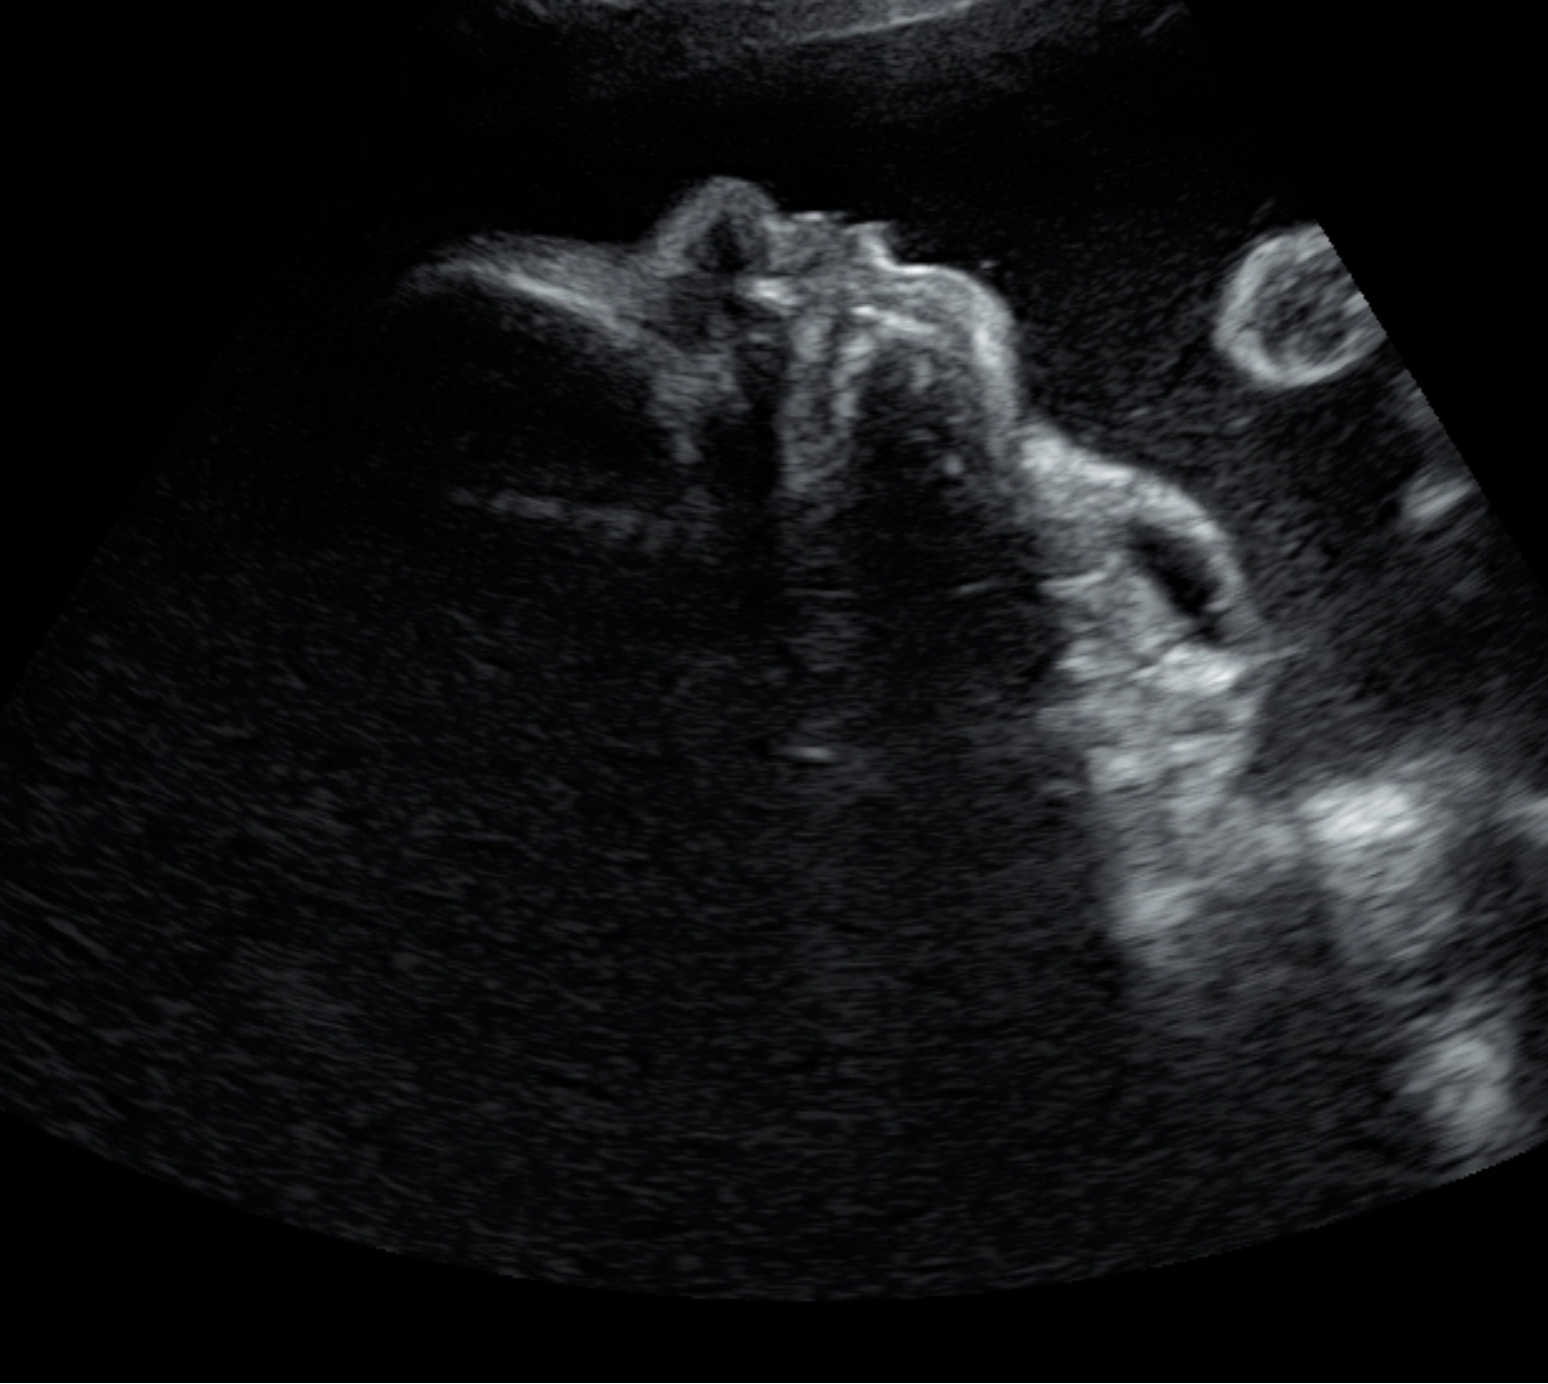

The sonogram shows a fetal head and the cervical area of the fetus in a sagittal plane. One can see that the fetal neck has a huge area with teratoma which has a size about 8x10 cm. Furthermore, one can see the fetal profile with chin and fetal nose.

Teratomas are rare fetal tumors with a frequency of 1: 20,000 to 1: 40,000 live births. Histologically, these are benign tumors formed by the three germ layers (ectoderm, mesoderm and endoderm). While most of the fetal teratomas are manifested in the coccyx region, cervical teratomas account for only about 6% of congenital teratomas. The main problems in pregnancy and perinatal period are the increase in size, the resulting impairment of fetal swallowing with consecutive polyhydramnios and significantly increased risk of premature birth and birth the difficulty postnatally to secure the respiratory tract.